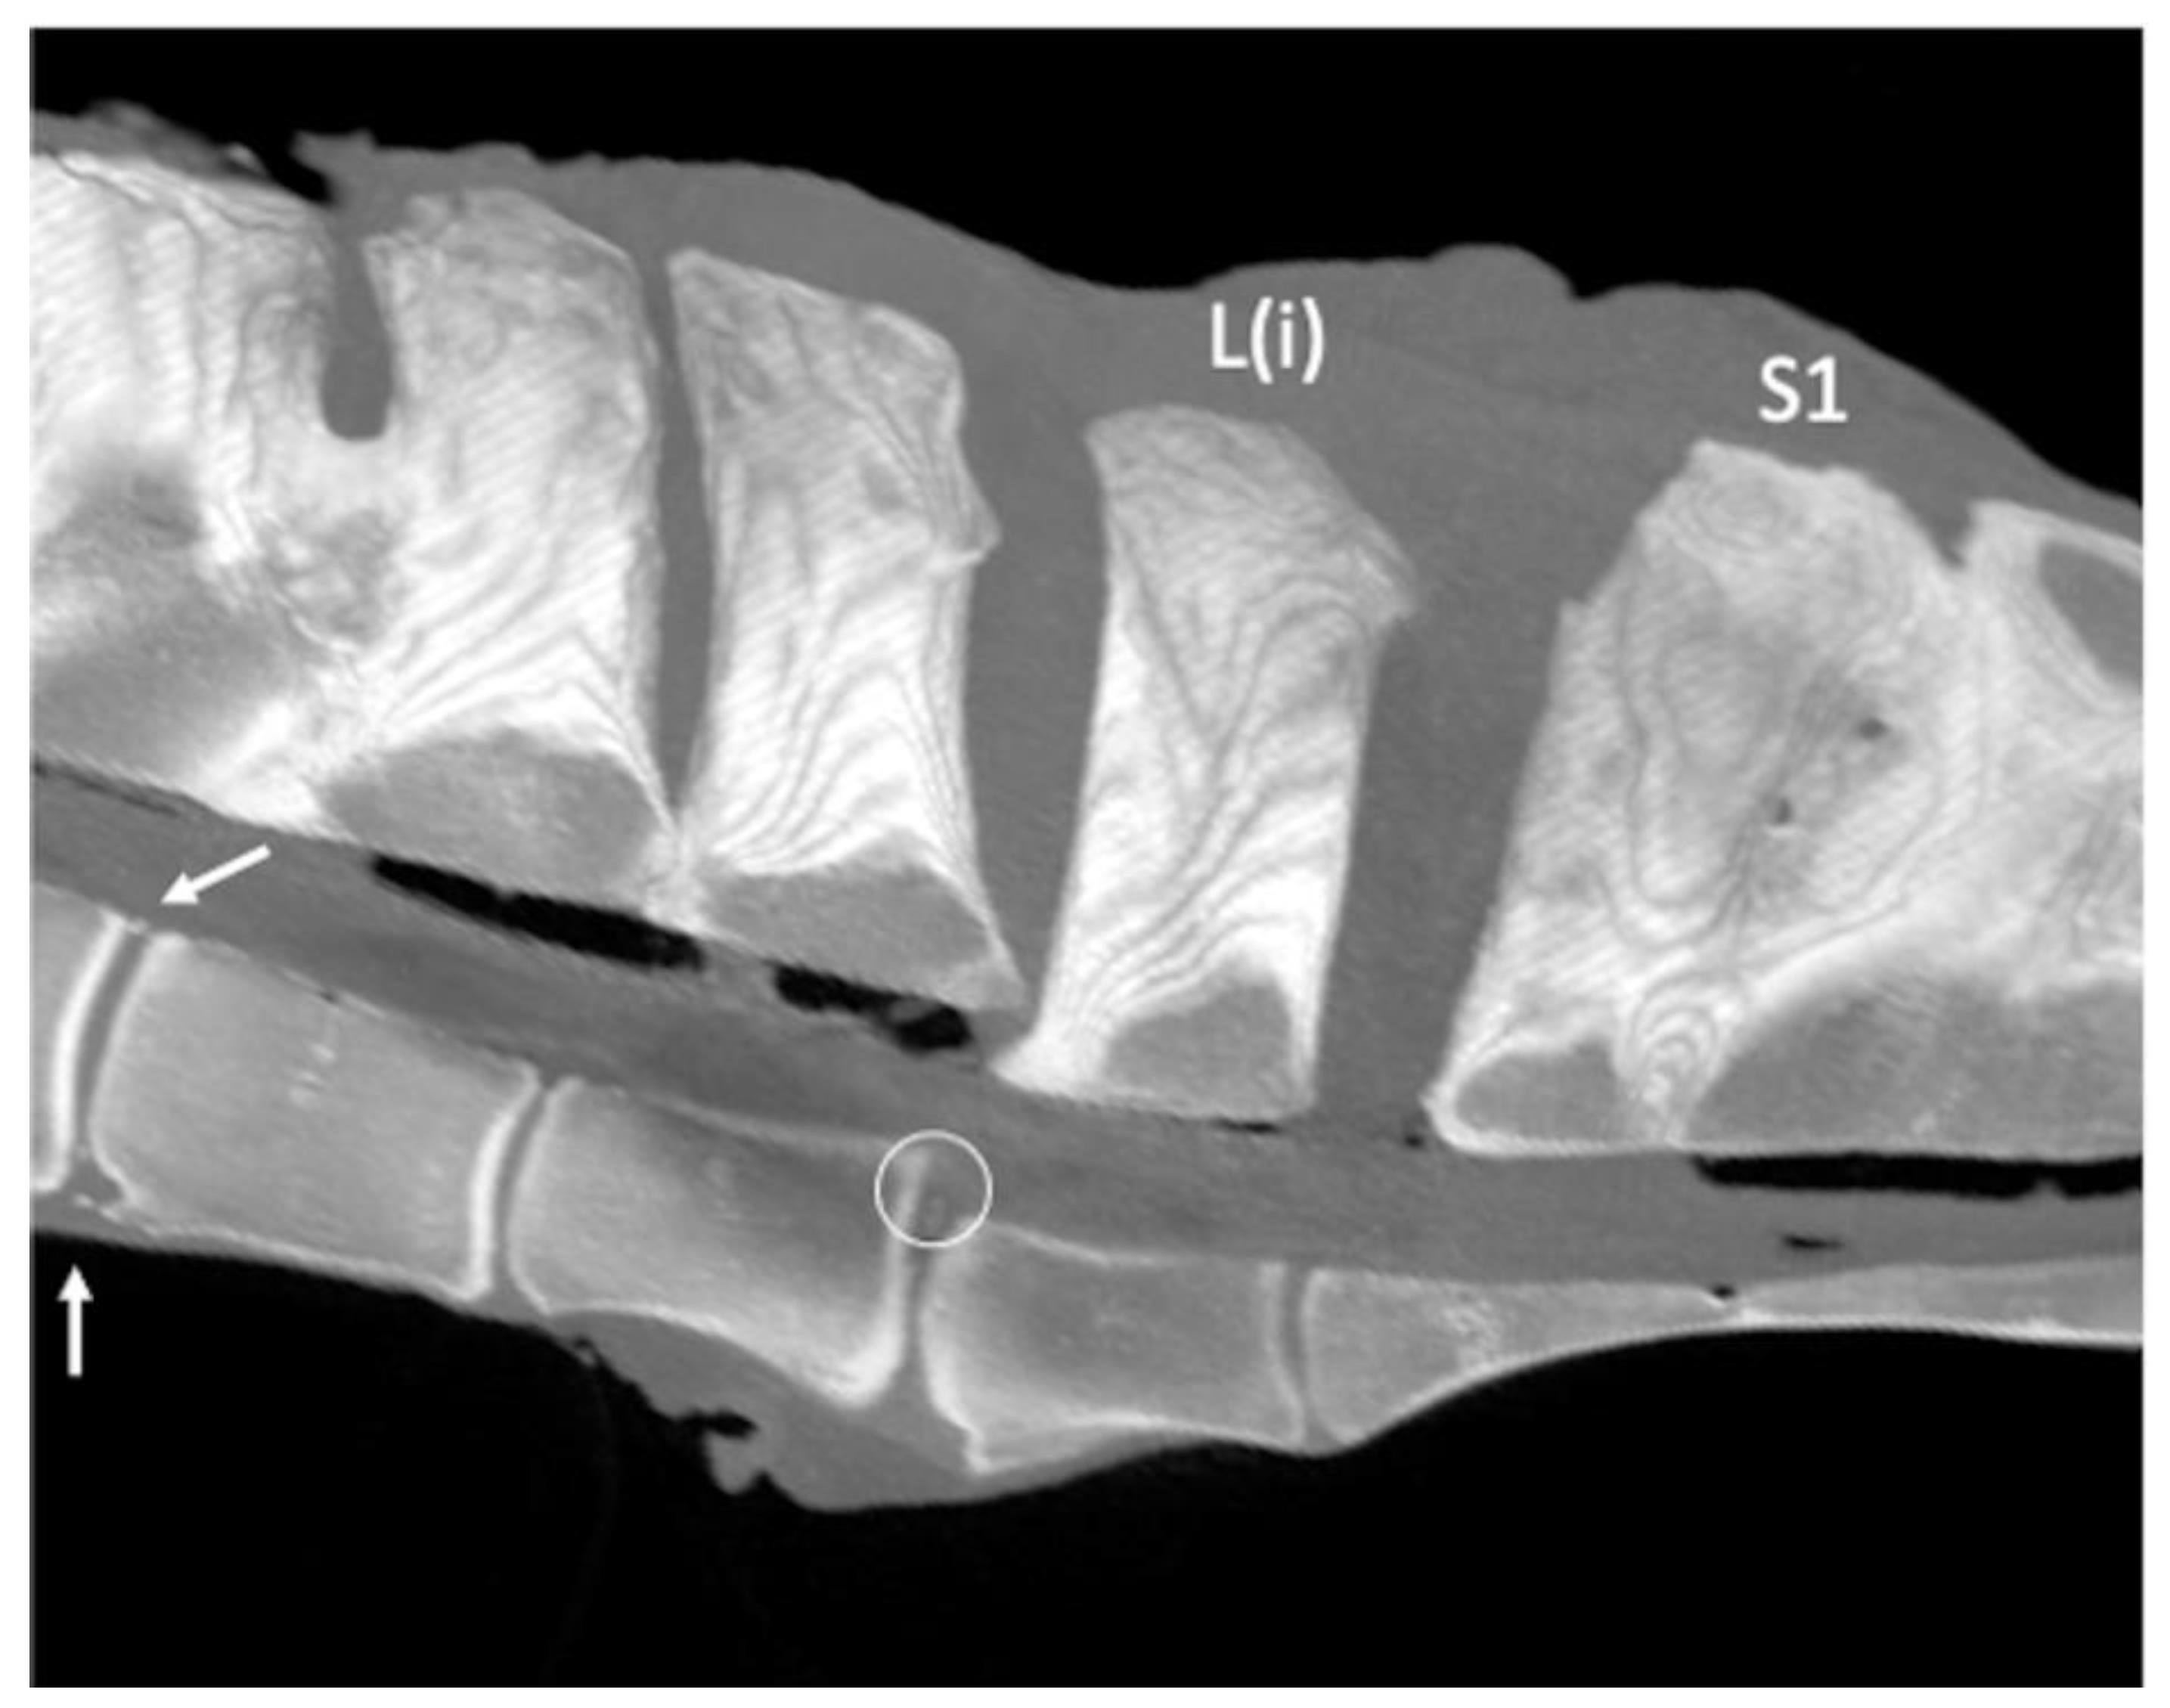

Ventral spondylolisthesis involving L(i) and the sacrum was found in one specimen, concurrently with a marked change in the L(ii)-L(i) disc and the presence of two small circular hyperattenuating structures attributable to disc mineralization (Figure 7).

Spondylolisthesis was observed in concomitance with bilateral severe osseous changes of the L(ii)-L(i) ITJs and APJs.

Figure 7. Sagittal multiplanar reconstruction computed tomographic image of the lumbosacroiliac specimen 1 using maximum intensity projection (MIP) (cranial is toward the left) showing the presence of a ventral displacement of L(i) and sacrum relative to the more cranial lumbar vertebrae (ventral spondylolisthesis). Note two small hyperattenuating structures at the level of the dorsal portion of the intervertebral disc (circle), L(iv)-L(iii) intervertebral osteophytes (white arrows) on both the dorsal and ventral aspects, and L(iv)-L(iii) spinous processes (SPs) fusion, as well as a fusion of the sacral SPs. L(iv): fourth to the most caudal lumbar vertebra; L(iii): third to the most caudal lumbar vertebra; L(ii): second to the most caudal lumbar vertebra; L(i): the most caudal lumbar vertebra; S1: the first sacral vertebra.